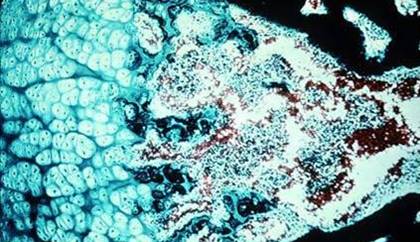

Fig. 2 Tesut osos spongios. Traveele osoase se anastomozeaza delimitand spatii largi ocupate cu tesut mieloid

Fig. 3 Tesut osos spongios in lumina polarizata.